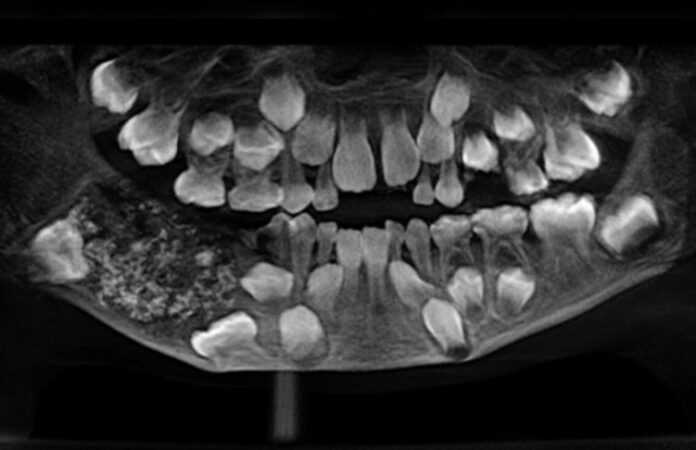

Em 2019, durante uma cirurgia no Saveetha Dental College and Hospital, os médicos encontraram 526 dentes em miniatura dentro de uma massa localizada na mandíbula do garoto.

A cirurgia retirou uma massa de cerca de 200 gramas, que continha uma espécie de bolsa fechada repleta de pequenas estruturas semelhantes a dentes. O material passou por análise detalhada, confirmando a presença de centenas de “dentículos” agrupados.

Segundo o hospital, foram necessárias cinco horas de trabalho minucioso para remover todos os dentes em miniatura, que lembravam “pérolas dentro de uma ostra”.